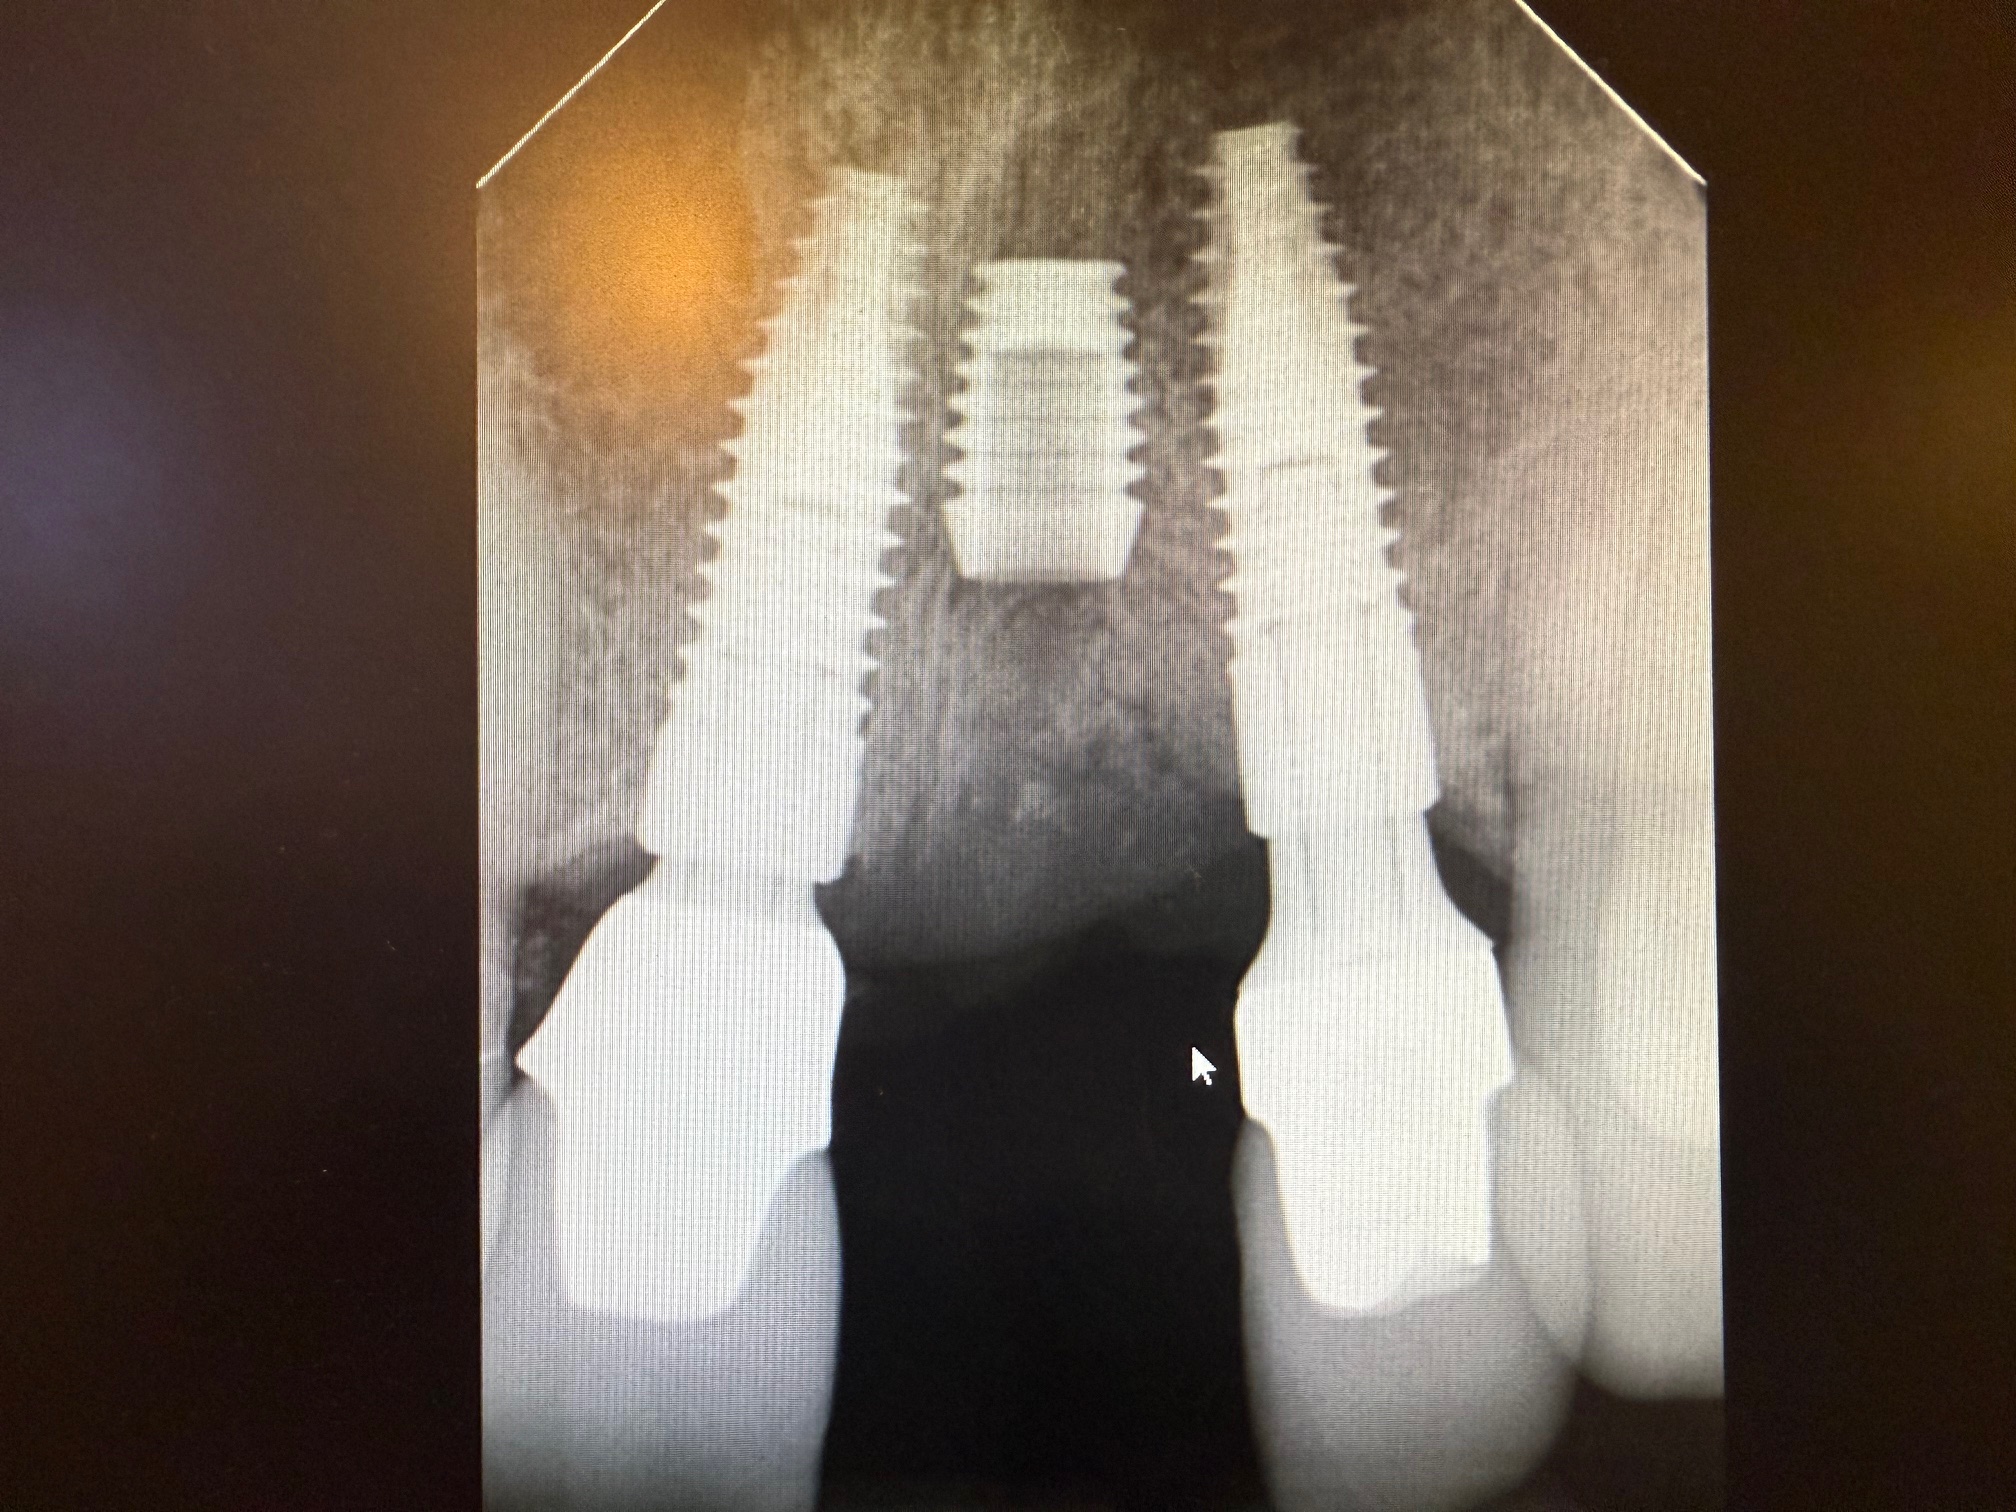

バイコンインプラントは、インプラント間距離が1mm程度あれば

打ち込むところに特殊性があります。

過度に骨を圧迫しないで埋入するので、隣のインプラントと近くて

他社製品を使って、この場所にインプラントをすることは不可能で

ちなみにこの他社インプラント間の埋入は、初めてのケースです。

10年前なら無理でしたね。